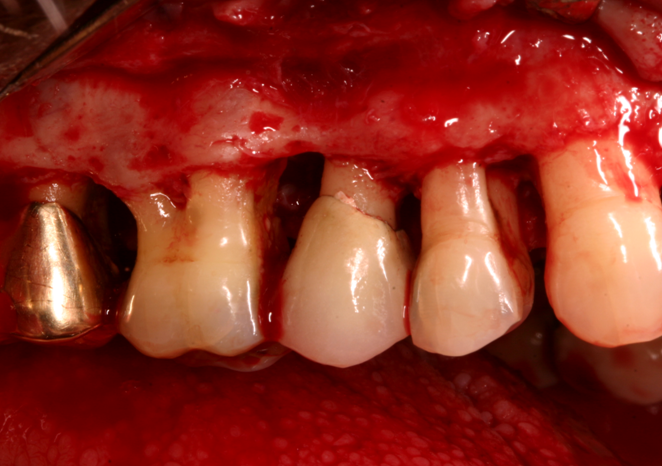

Fig :Periodontal flap surgery.

In addition to scaling and polishing advance treatment such as flap surgery , gingival depigmentation, correction of gum recession and bone loss is provided.